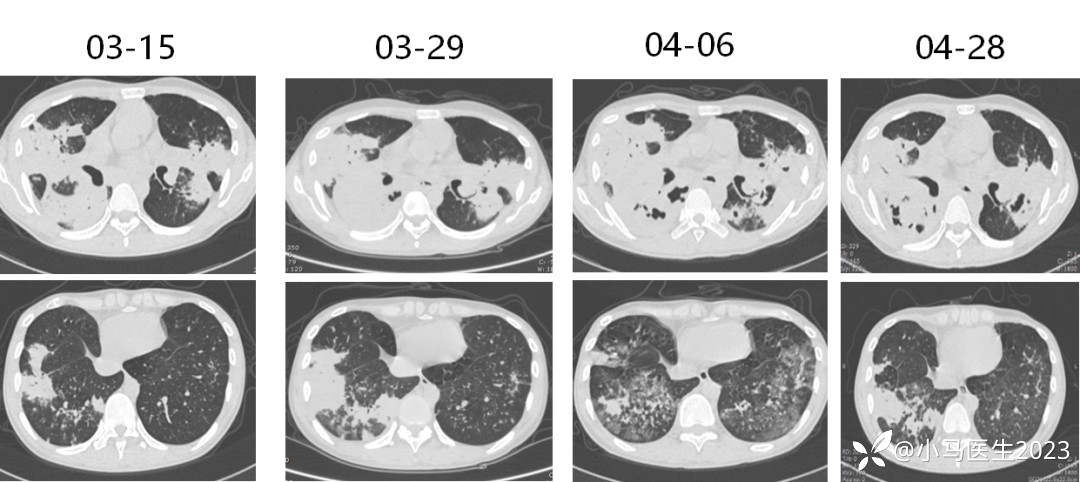

03-29复查胸部CT进展

胸部CT对比

04-06 胸部CT仍进展

2021-04-28胸部CT进展,空洞形成

换用两性霉素B脂质体

05-12

05-27

对比